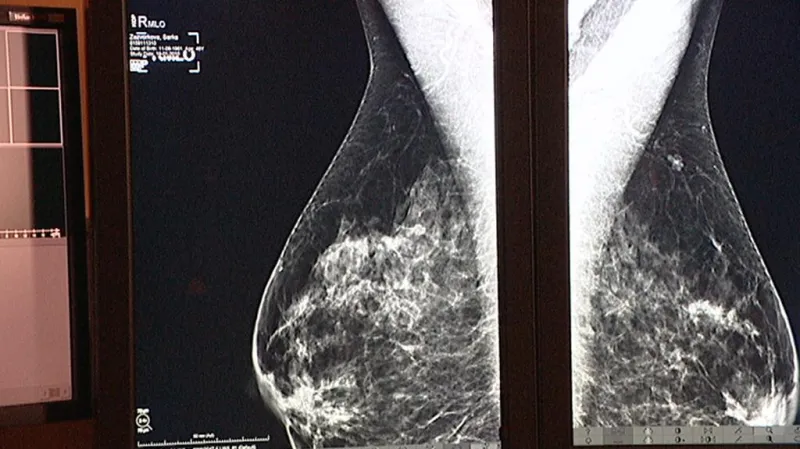

Jiná, konzervativnější možnost pak je zvolit si pravidelné kontroly pomocí magnetické rezonance, ultrazvuku a mamografie. Toto dokonalé sledování podle Tesařové vede většinou k tomu, že se nádor zachytí včas a je pak lépe léčitelný.

Ženám od 45 let věku v ČR hradí zdravotní pojišťovny jednou za dva roky vyšetření na mamografu. Pro mladší ženy není vhodné, vyšetřují se magnetickou rezonancí. Podle doporučení odborníků by si ženy měly prsa samy vyšetřovat pohledem i pohmatem každý měsíc.